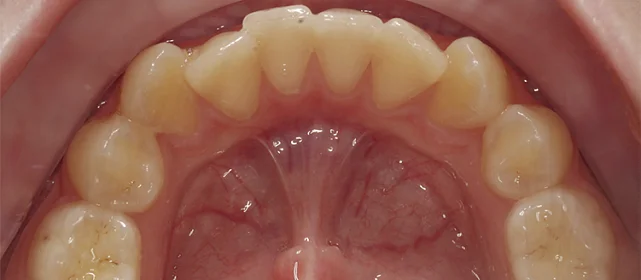

Нарушение соотношения челюстей и неправильное положение зубов — зубные ряды смыкались некорректно, зубы стояли со смещением.

Проблема: Пациентку не устраивало положение зубов и то, как смыкаются челюсти. Зубы стояли неровно, ряды сходились неправильно.